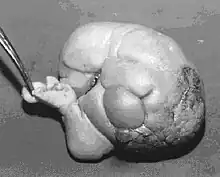

Fetus in fetu (or foetus in foetu) is a rare developmental abnormality in which a mass of tissue resembling a fetus forms inside the body of its twin. An early example of the phenomenon was described in 1808 by George William Young.[1]

A fetus in fetu can be considered alive, but only in the sense that its component tissues have not yet died or been eliminated. Thus, the life of a fetus in fetu is akin to that of a tumor in that its cells remain viable by way of normal metabolic activity. However, without the gestational conditions in utero with the amnion and placenta, a fetus in fetu can develop into, at best, an especially well differentiated teratoma; or, at worst, a high-grade metastatic teratocarcinoma. In terms of physical maturation, its organs have a working blood supply from the host, but all cases of fetus in fetu present critical defects, such as no functional brain, heart, lungs, gastrointestinal tract, or urinary tract. Accordingly, while a fetus in fetu can share select morphological features with a normal fetus, it has no prospect of any life outside of the host twin. Moreover, it poses clear threats to the life of the host twin on whom its own life depends.[4]

Fetus in fetu may be a very highly differentiated form of dermoid cyst, itself a highly differentiated form of mature teratoma.[5]